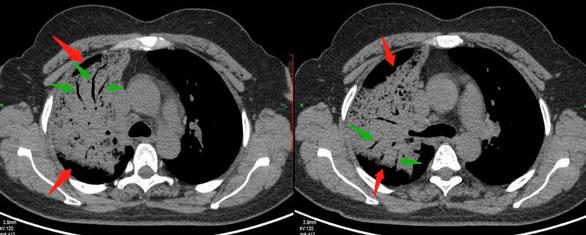

比如这一位病人,巨块型肝癌,确诊的时候肿瘤就比拳头还要大了。

这种程度如果不治疗会快速进展,一般寿命不超过三个月,短的甚至只有二十几天。曾经肝癌被称作“癌中之王”,就是这个原因。

当然这个病人没有放弃治疗,选用介入栓塞配合消融治疗,三年半后还活着:

这个病人比较幸运,对治疗有效!并且三年多的时间没有发生转移和复发。